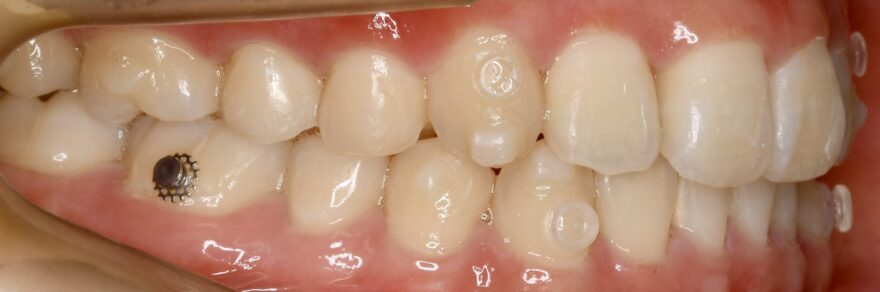

治療中の口腔内写真

インビザラインと他社製マウスピース矯正との違いにアタッチメントがあります。

歯の表面に付与する白くて小さい突起がアタッチメント。

アタッチメントとマウスピースが噛み合うことで、

・回転

・垂直移動

・水平移動

などといったマウスピース単体では苦手とされる、歯の3次元的な移動が可能となります。